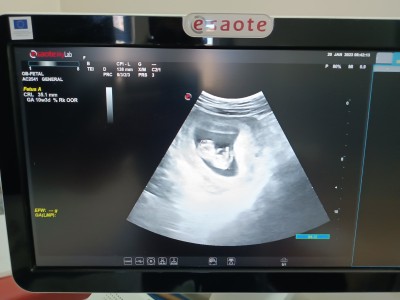

12+1 tahmin edelim acaba neyin nesi bu

ilk bebeğim cinsiyet tahmini kızlar çok heyecanlıyım

12+1